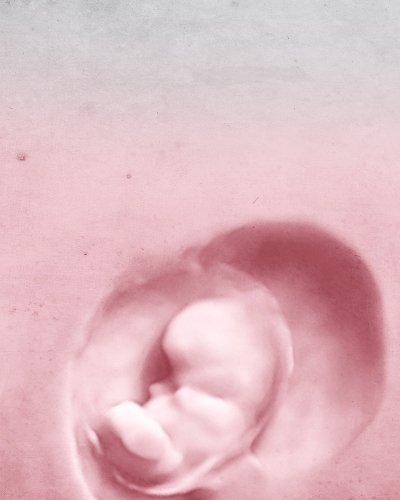

La recherche nous donne la vie

Nous vous aidons à former votre famille

Nous garantissons votre grossesse ou nous vous remboursons la totalité du montant. Voulez-vous?